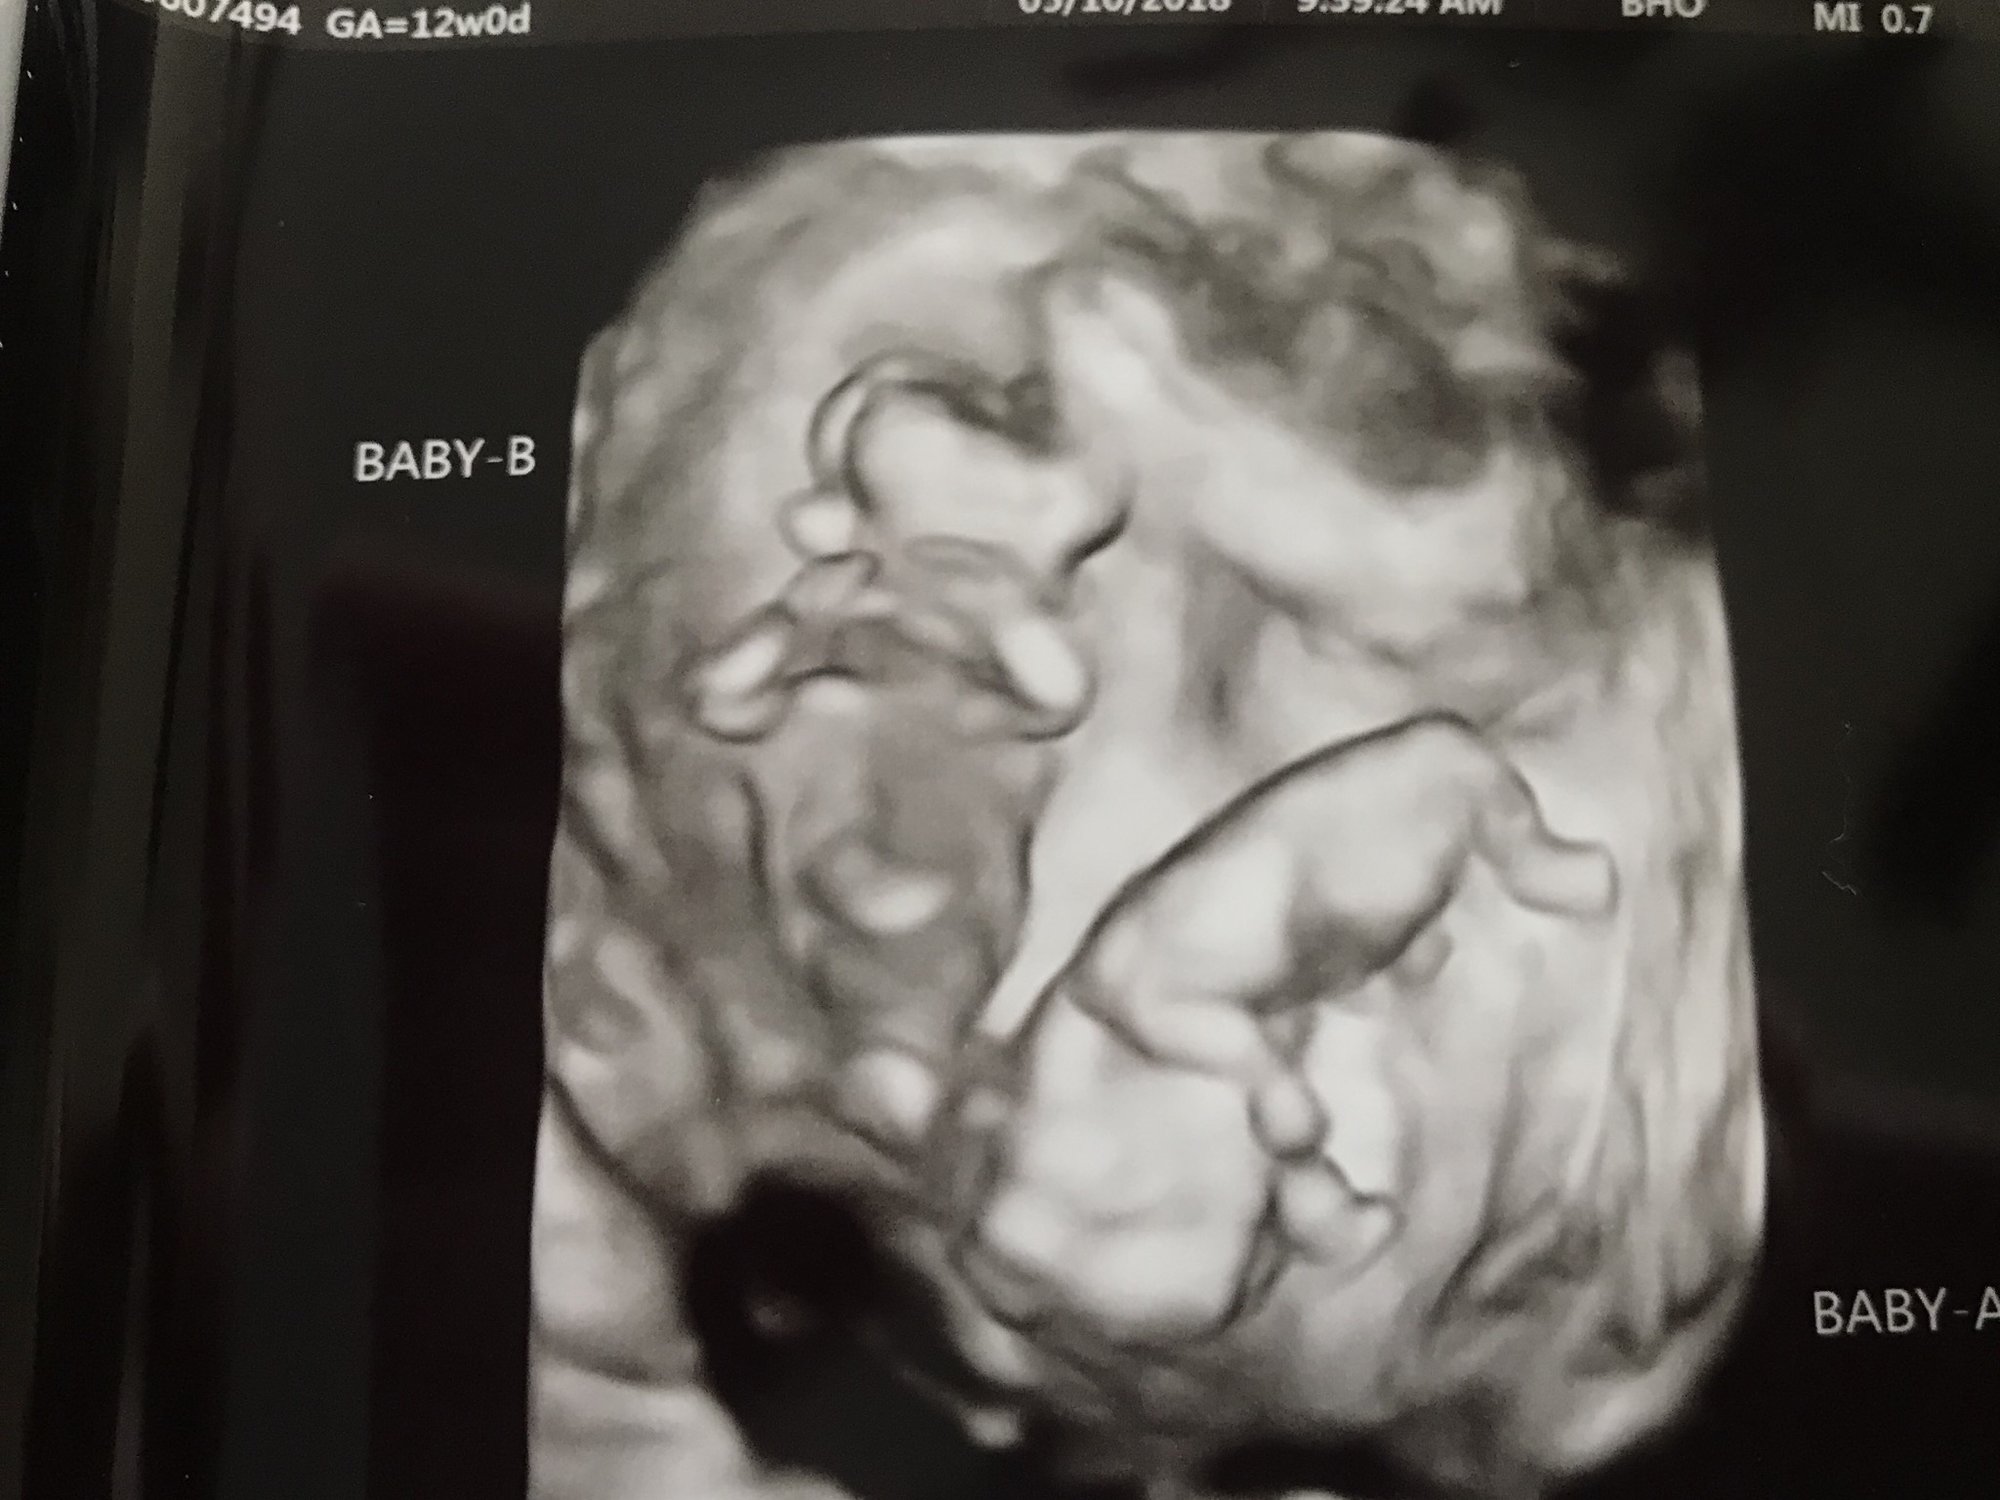

excited to finally get a pic up here! from this morning, confirmed identical twins, 12w exactly and measuring right on track. both were camera shy, but also cooperative for the ultrasound tech (rolled over at the right time). apologies to those who hate 3d pics, but this was the only pic i got of both at the same time.